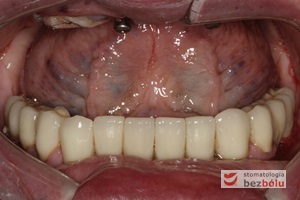

Ostateczny efekt estetyczny wieńczący proces terapeutyczny - odbudowa protetyczna obu łuków zębowych przy zastosowaniu implantów Friadent Ankylos

Ostateczny efekt estetyczny wieńczący proces terapeutyczny – odbudowa protetyczna obu łuków zębowych przy zastosowaniu implantów Friadent Ankylos

Pozytywna przemiana uśmiechu - odbudowa protetyczna na implantach - obraz kliniczny po terapii stomatologicznej

Pozytywna przemiana uśmiechu – obraz kliniczny po terapii stomatologicznej